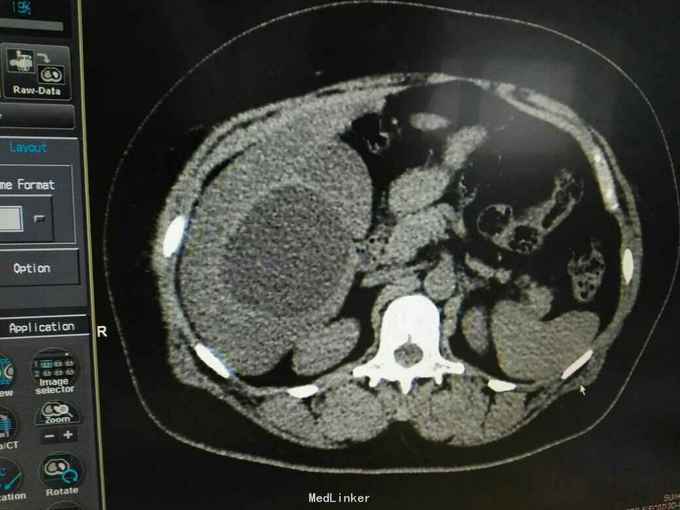

巨大肝囊肿

发现肝脏占位10年

肋弓下可触及囊性占位

肝囊肿

今日在局麻下行囊肿穿刺抽吸+无水酒精注射术 术中共抽取淡黄色液250ml